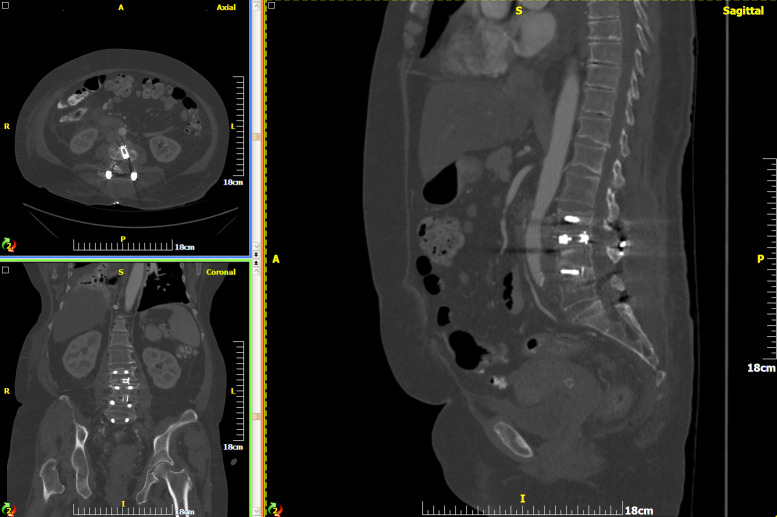

Abstract Image